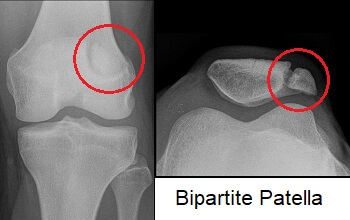

무릎이나 다른 뼈에서도 골절과 혼동하지 말아야할 것들이 몇가지 있는데 골이 fused 되지 못할 때 이러한 증상이 있을 수 있습니다.